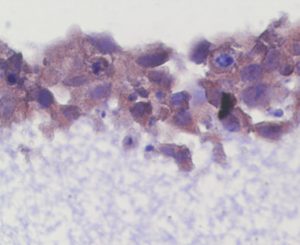

Mehr erfahren zu: "Schleim-Moleküle können Pilzinfektionen vereiteln" Schleim-Moleküle können Pilzinfektionen vereiteln Candida albicans besiedelt die Schleimhäute der meisten gesunden Menschen, kann aber auch Infektionen verursachen. Forschende haben Moleküle im Sekret der Schleimhäute identifiziert, die den Pilz daran hindern, schädlich zu werden, […]